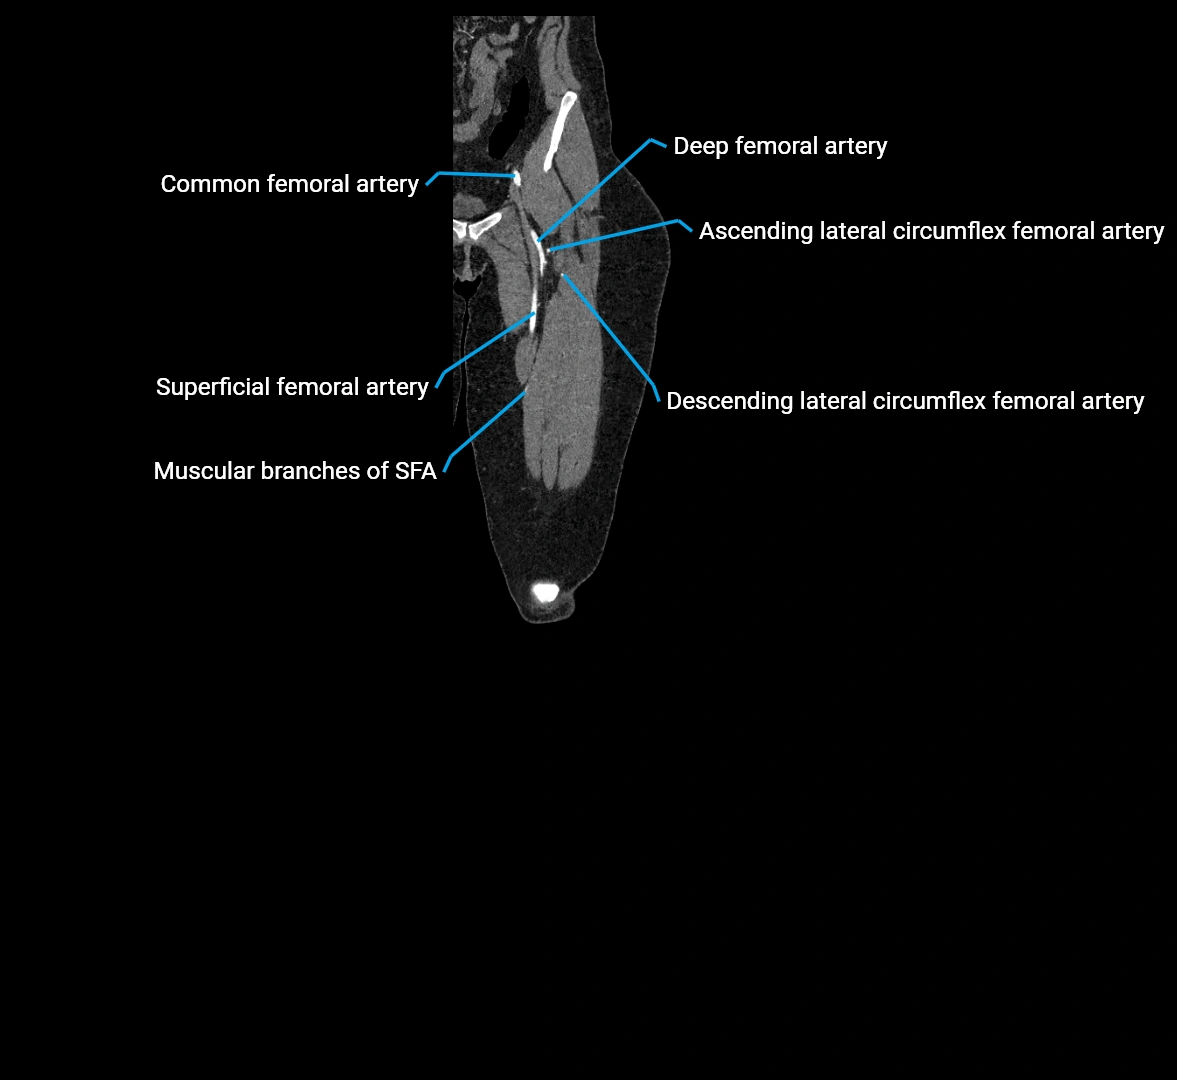

Contrast-enhanced CT (CTA):

• Gold standard for abdominal aortic imaging

• Provides excellent detail of lumen, wall, aneurysm, thrombus, and branch vessels

• Multiplanar and 3D reconstructions help in aneurysm measurement, stent graft planning, and dissection evaluation

• Detects acute rupture, traumatic injury, or occlusion with high sensitivity